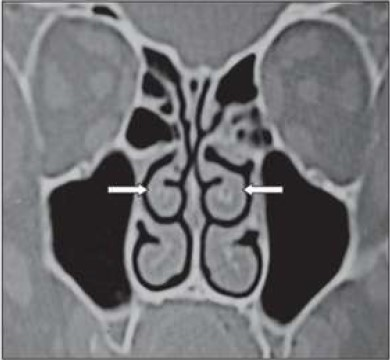

Na figura acima, de uma tomografia computadorizada dos seios paranasais, é possível observar na ponta da seta: